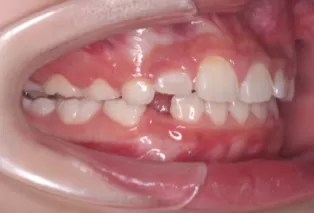

Photos intra-orales